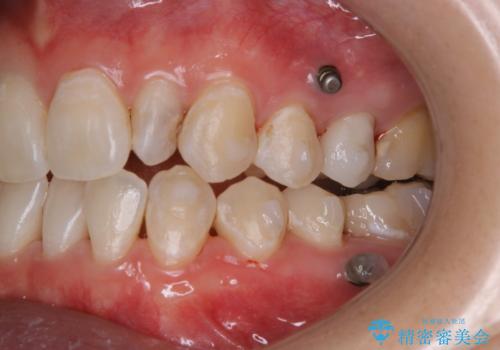

インビザライン矯正中にPMTCでコーヒーによるステインの除去

- コーヒーを毎日頻繁に飲むため、ステインがついてしまうとのことでした。全体的に頑固なステインの付着が見られたため、PMTC60分コースを行いました。

PMTC(保険外治療)は、毎日の歯磨きで落としきれない汚れや、コーヒ、紅茶・タバコのヤニなどの着色も除去します。目には見えない歯と歯の間・歯肉の境目・インビザライン中はアタッチメント周囲などに残っているプラーク(歯垢)もしっかり取り除きます。PMTCでは専門的な機械や材料を使用して、徹底的に汚れを除去するため、虫歯・歯周病・口臭予防などにつながります。

また、仕上げのトリートメントでは歯の表面の凸凹にミネラルを補給して、ツルツルの表面に仕上げます。定期的にPMTCを行うことにより、歯質の強化になり着色がつきにくい状態になります。